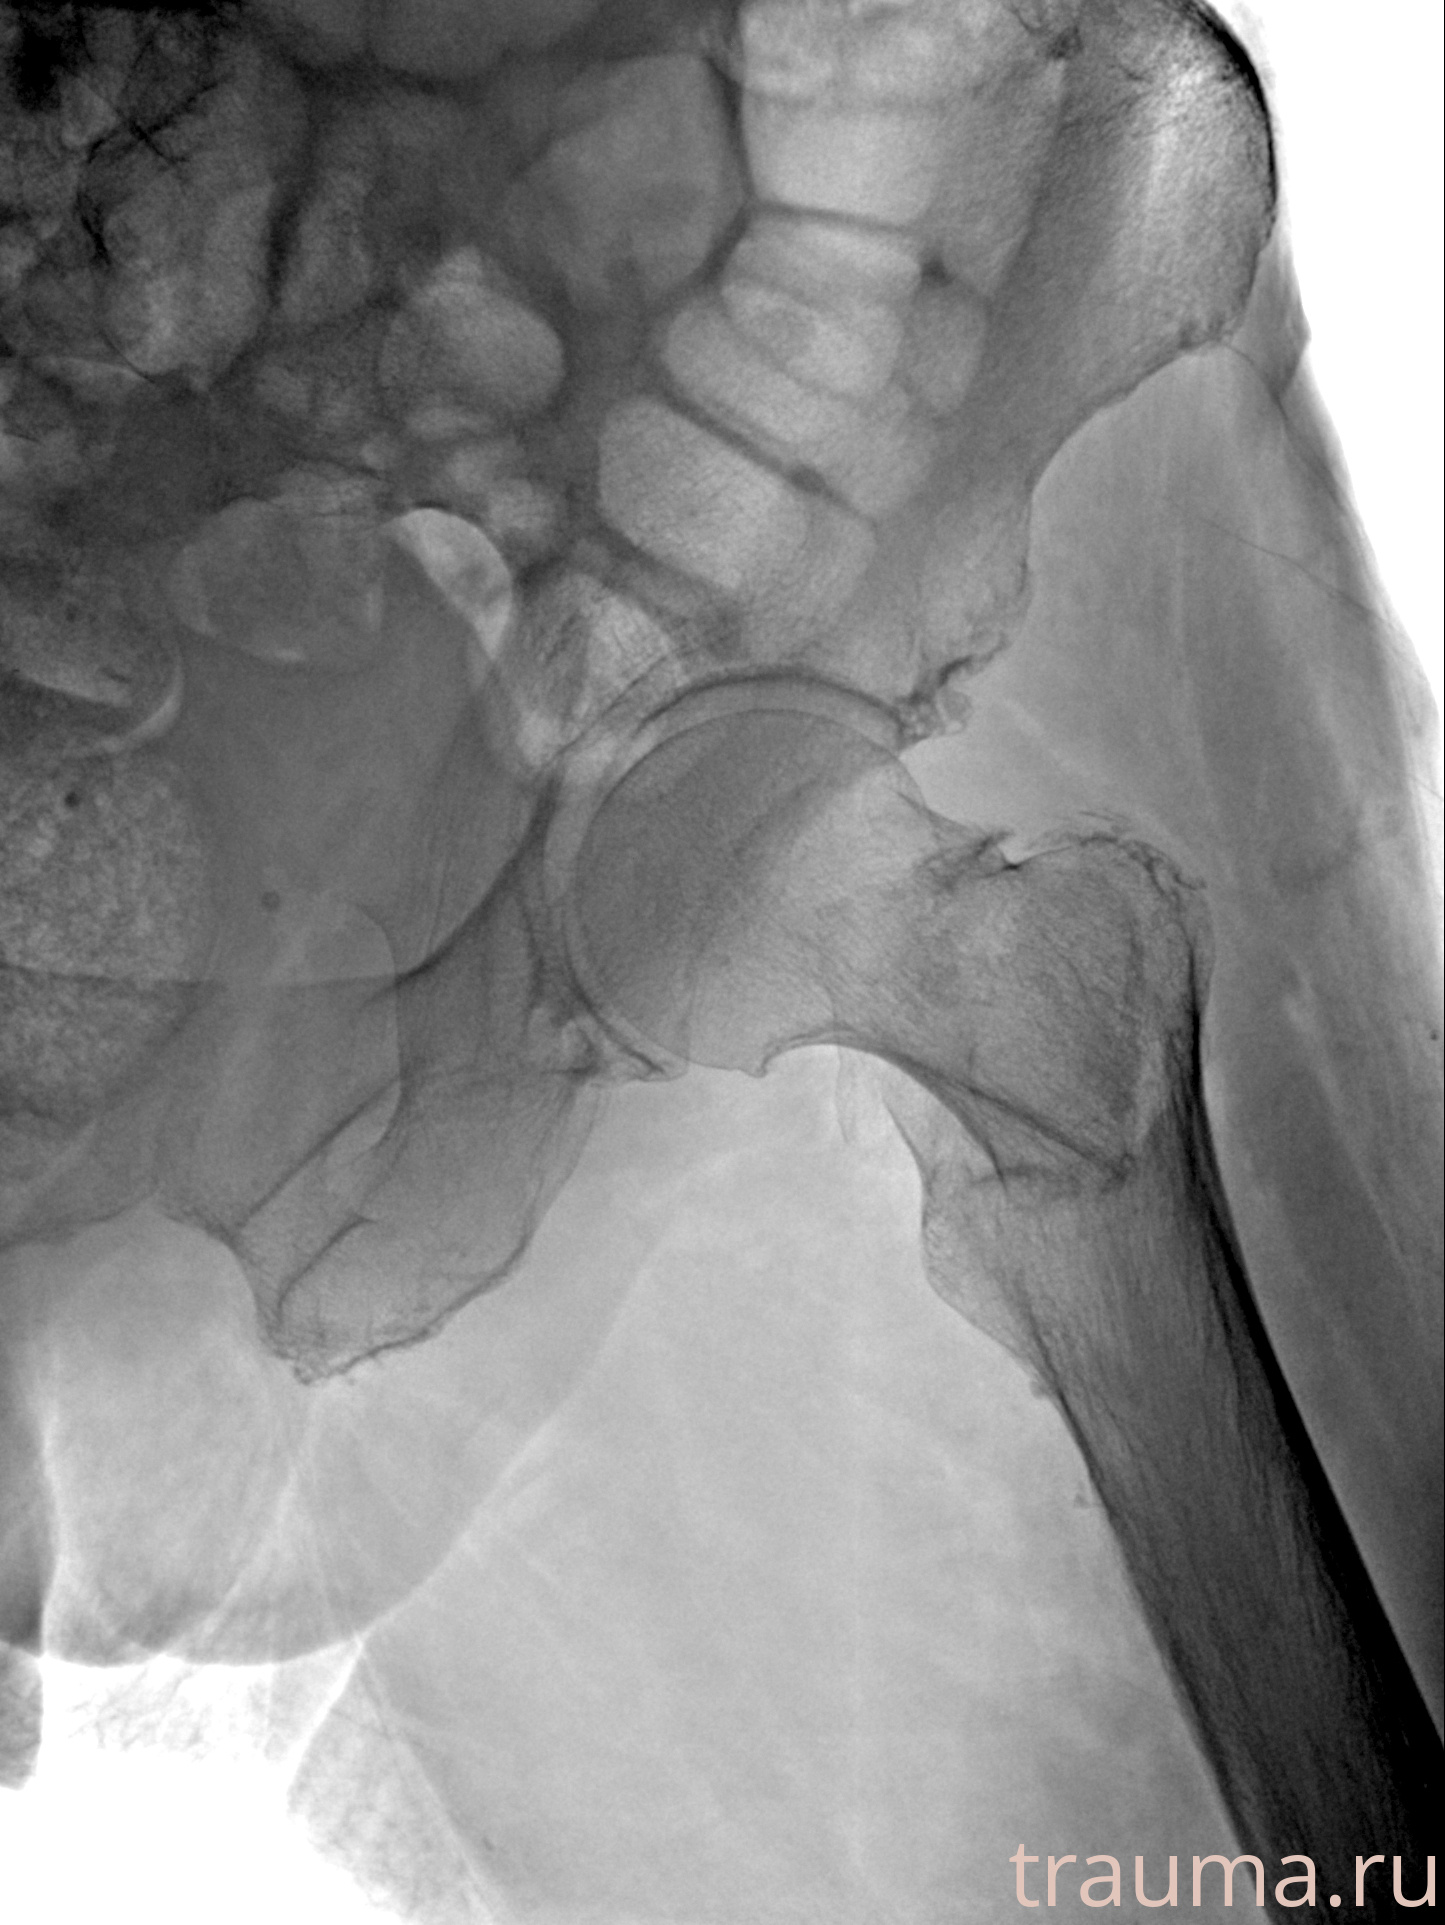

Рентгенограммы